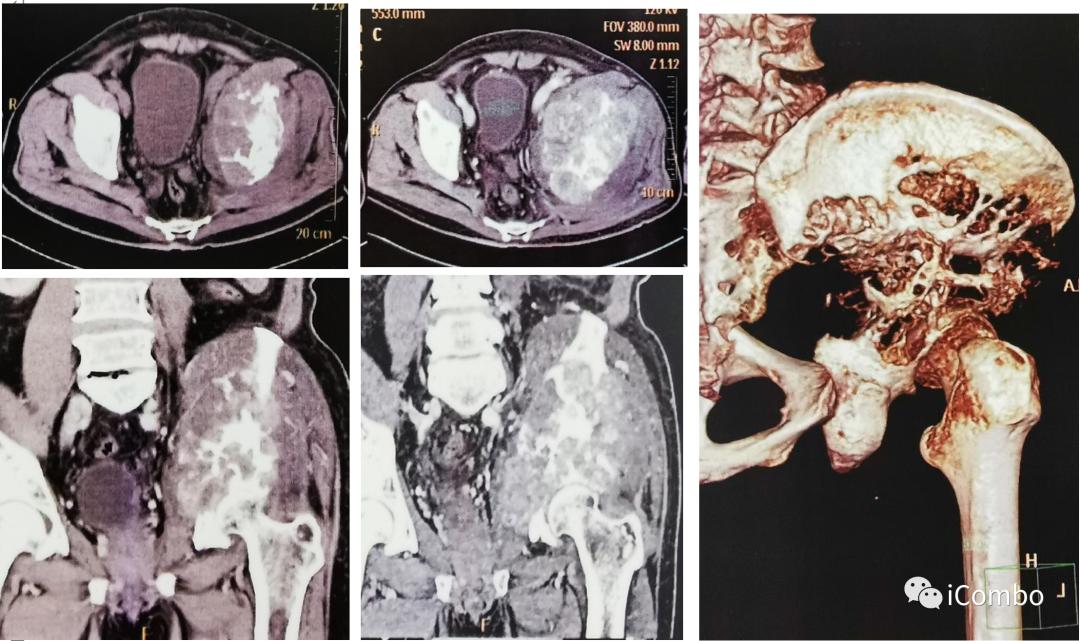

现病史:2012年行左肾癌根治术(肿瘤最大径7厘米),2018-9左髂部疼痛不适,考虑转移瘤,行索坦治疗。2019-06发现左胫骨肿块。2019-7-18 CT示肿瘤较前进展(107*84mm)。

1、2019-7-22泌尿肿瘤多学科会诊,考虑肿物过于巨大,局部联合治疗,更换药物给予二线靶向联合免疫,肿物缩小后再联合局部放疗。

2、2019-8-9患者对药物耐受性不佳,疼痛较前加重,蛋白尿增加至3+,血RBC:2.56×10E12/L,Hb:80g/L,予以对症处理。2019-8-23:血RBC:3.09×10E19/L,Hb:87g/L,局部消融治疗。

2019-10-8复查:肿物较前缩小

2020-1-8 较11-22肿物较前增大